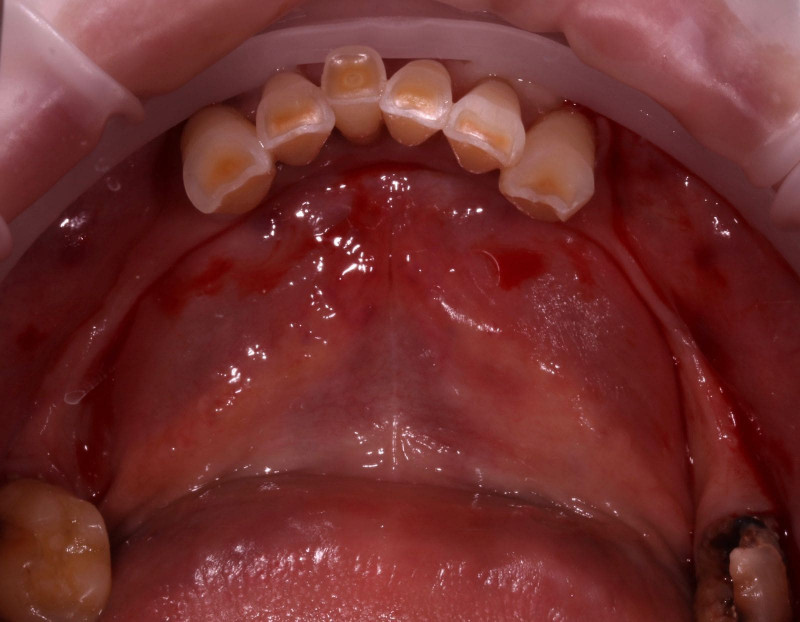

2 работы в портфолио